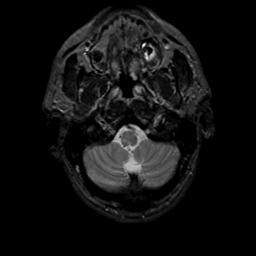

MR Study #20 October 6, 1991 -- Slice #5

[Home][Help][Clinical][Tour 1][Tour 2] Slice 5